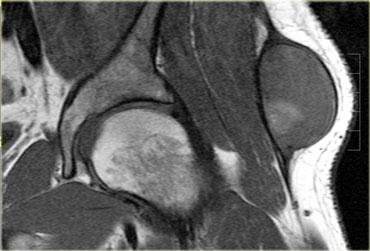

Bên trái là ví dụ về một vết rách ở cơ ngực lớn bên trái.

Trên ảnh T1 có trọng số, có một khoảng hở trong cơ với một lượng nhỏ mỡ lấp đầy vào đó.

Chuỗi xung gradient echo cho thấy sự tích tụ dịch khu trú và một số tăng tín hiệu trong cơ.

Tổn thương trông có vẻ không nghiêm trọng.

Tuy nhiên, khi được yêu cầu co cơ ngực hoàn toàn, có thể thấy rõ sự bất đối xứng do đứt hoàn toàn cơ (mũi tên xanh).

Về mặt lâm sàng, đây là tổn thương độ 3, với mất chức năng hoàn toàn của cơ.